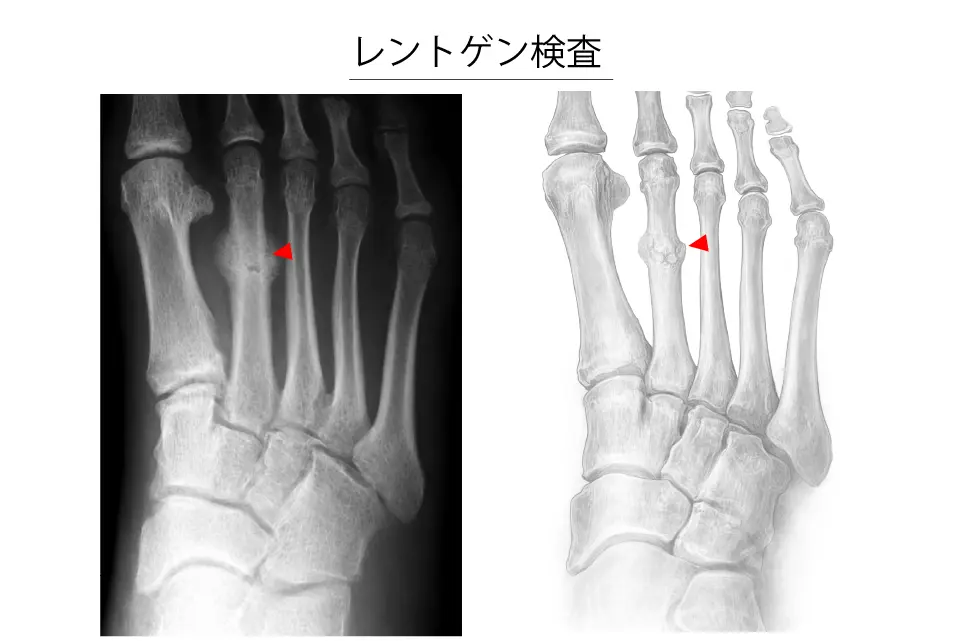

レントゲン検査(整形外科による)

- 初期では骨折線が不明瞭で見逃されることがある

- 経過を確認するための再検査が有用

- 必要に応じて斜位を含めた多方向撮影を行う